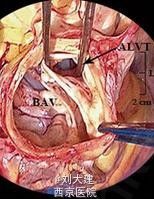

心脏超声和多层 CT 血管造影发现一隧道样结构,伴收缩期顺流和舒张期逆流,该结构起源于主动脉根部,刚好位于扩张的主动脉窦水平之上,缠绕左下进入左心室。最终诊断为 II 型 ALVT(以隧道结构的心脏外主动脉壁动脉瘤伴或不伴瓣膜变形为特征),术中探查后明确诊断,手术关闭隧道后患者表现良好。